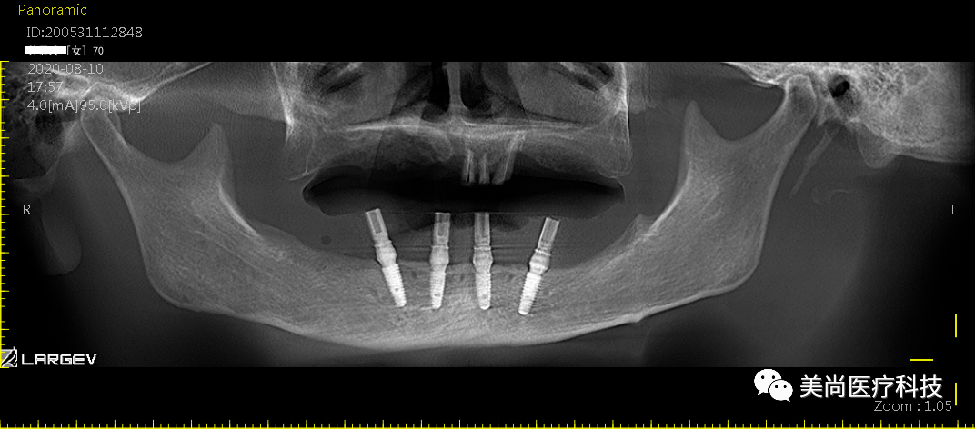

上颌可见烤瓷连桥修复Ⅲ°松动,牙龈微红肿;

下颌无牙颌附着龈狭窄仅1mm,牙槽嵴呈刀刃状;

32、42可用骨宽度6mm,可用骨高度10mm;

34、44可用骨宽度6mm,可用骨高度11.5mm。

制作导板,导板引导下植入种植体

导板下植入植体:

在32、42处植入3.5*10mm植体各一颗,植入扭矩约35n.cm;

在34、44处植入4.0*11.5mm植体各一颗,植入扭矩约40n.cm。